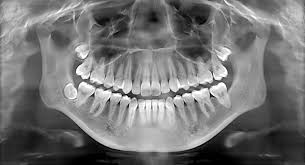

Panoramic X-rays capture a wide-angle view of the entire mouth, including the teeth, jaws, and surrounding structures. This comprehensive imaging is essential for identifying issues that might not be visible with standard intraoral X-rays, such as impacted teeth, jaw disorders, and sinus problems.

These X-rays provide clear, detailed images, aiding in the diagnosis of complex dental conditions. Dentists can detect fractures, cysts, tumors, and other abnormalities that could significantly impact oral health. This enhanced clarity ensures accurate diagnosis and effective treatment planning.